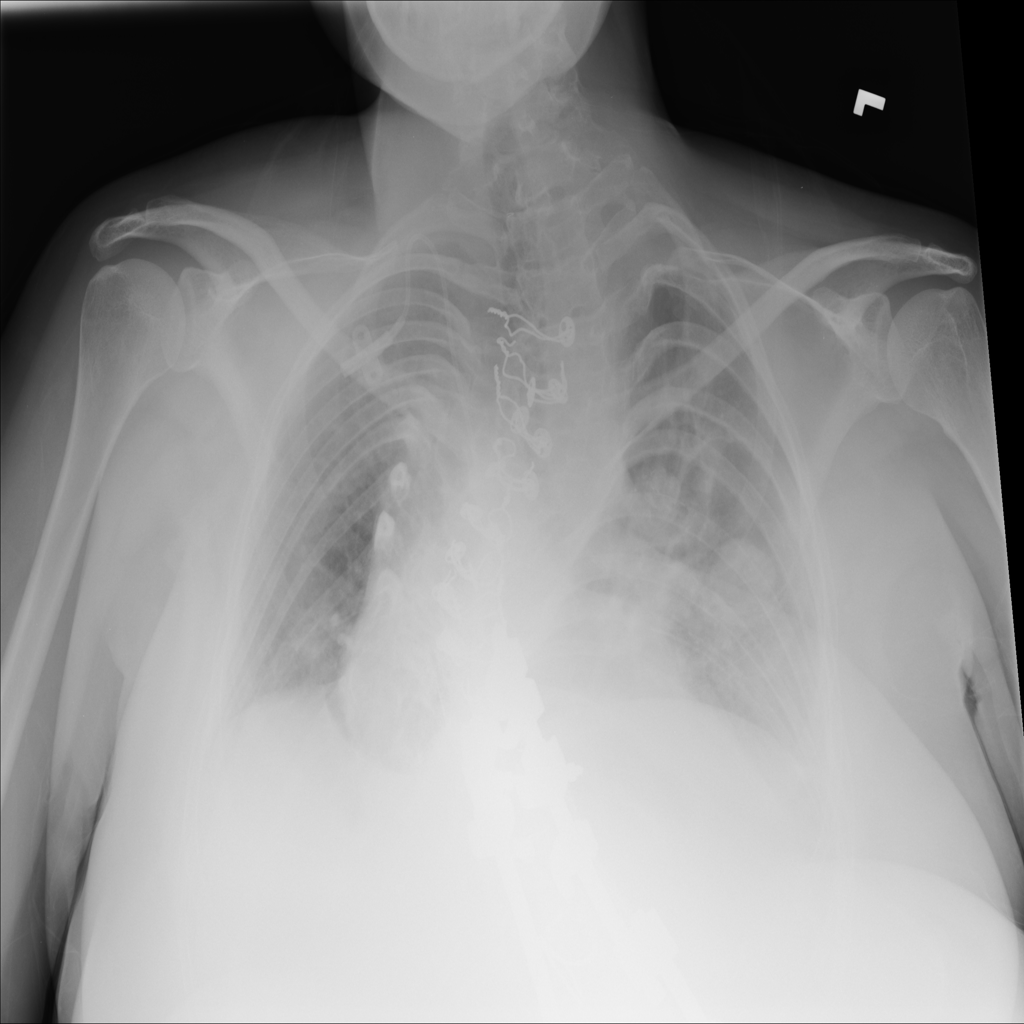

Mass

A mass is a larger focal opacity or lesion seen on the image. It is a descriptive finding that can have several causes and usually needs more imaging or clinical context to characterize.

PAT-4639 · IMG-024Mass

PAT-4639 · IMG-024

AP